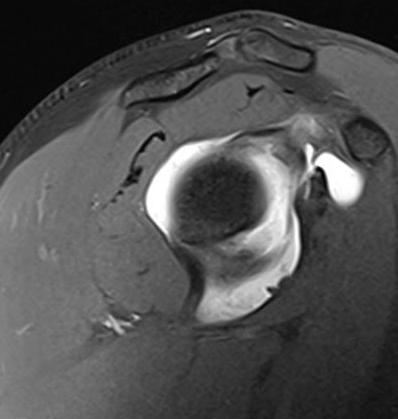

Se identifica un quiste paralabral lobulado de 3.4 x 2.3 cm en la escotadura espinoglenoidea, sin comunicación aparente con la articulación glenohumeral.

Figura 2: Secuencia axial PD-FS: quiste bilobulado en la escotadura espinoglenoidea.